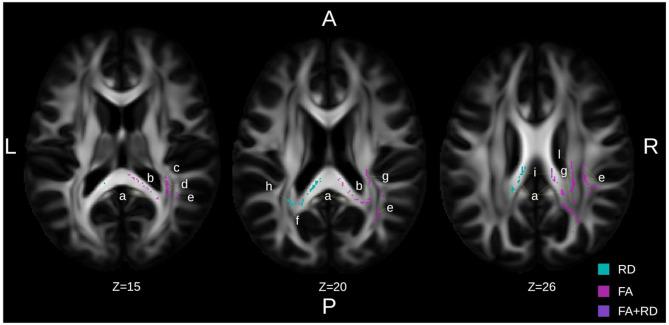

Complete datasets from 30 study participants (72.0 ± 8.6 years; 27% females) were available. 87% of participants had biomarker-supported characterization of mNCD etiology– mostly Alzheimer’s (62%). Significant moderate to large effects (partial eta-squared = 0.109 to 0.187) on GM/WM volumes were observed in the right and total hippocampus, thalamus, and anterior cingulate cortex in favor of ‘Brain-IT’ training. Hippocampal and thalamic changes correlated with improvements in verbal delayed recall. Protective effects on WM integrity, which correlated with cognitive improvements, were also observed, mainly around the thalamic radiation and the corpus callosum.

可获得 30 名研究参与者(72.0 ± 8.6 岁;27% 为女性)完整的数据集。87% 的参与者具有生物标志物支持的 mNCD 病因特征描述——大多数为阿尔茨海默病(62%)。在右侧和总海马体、丘脑和前扣带回皮质观察到对 GM/WM 体积有显著的中度至大效应(偏 eta 平方 = 0.109 至 0.187),支持“Brain-IT”训练。海马体和丘脑的变化与言语延迟回忆的改善相关。还观察到对 WM 完整性的保护作用,这与认知改善相关,主要围绕丘脑辐射和胼胝体。